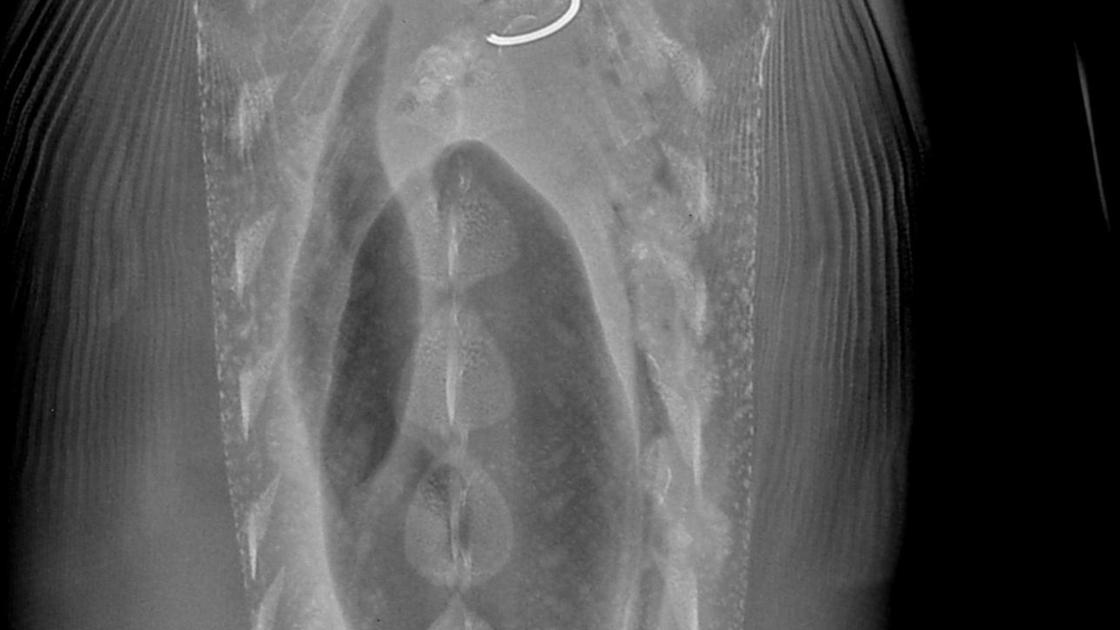

Fisheries biologists with the Idaho Department of Fish and Game and the Idaho Power Company scanned more than 2,000 sturgeon with metal detectors and used a portable X-ray machine on about 450 of them to document the prevalence of fishing tackle in the bellies of the fish.

They found about 21 percent of the sturgeon they examined had tackle in their bellies. Many of the sturgeon were captured multiple times during the four-year project. Recaptured fish with fishing tackle in their systems passed the metal in about 492 days on average. Recaptured fish ingested new metal about every 575 days on average.

The study, published by the American Fisheries Society, showed that fish with metal in their digestive tracts weighed slightly less than sturgeon of the same size without metal. However, the differences in weights were slight, suggesting the metal may affect their ability to feed or process food but not to a degree that would harm them on a population level.

The study also determined that most of the hooks and other fishing gear found in sturgeon were likely the result of the fish feeding on baited hooks that remained in the river after they had been snagged on rocks and broken off rather than from sturgeon deeply swallowing baited hooks still attached to fishing rods.